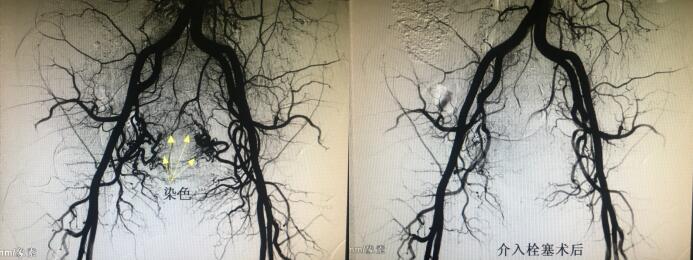

经人介绍来到乐鱼手机站入口介入科,经李建国主任术前评估,患者无介入手术禁忌症,于4月16日早9点行介入手术。术中采用右肱动脉穿刺、超选择双侧子宫动脉造影栓塞术,手术顺利历时约40分钟,成功保全了子宫。术后患者步入病房,避免了因卧床制动而形成下肢深静脉血栓的风险...